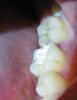

sway Опубликовано 26 августа, 2011 Автор Поделиться Опубликовано 26 августа, 2011 Может просочиться через негерметичную временную пломбу и вызвать некроз десны.ого. а это чем чревато? и как врач (или я) сможет это определить? я записан на вс, но пломбу снимать и чистить каналы не планировал (слишком непродолжительный срок для девит-с).Десна отечная и слегка болезненная при надавливании или чистке.Прилагаю фото зуба, сделал как мог.Что посоветуете? Ссылка на комментарий